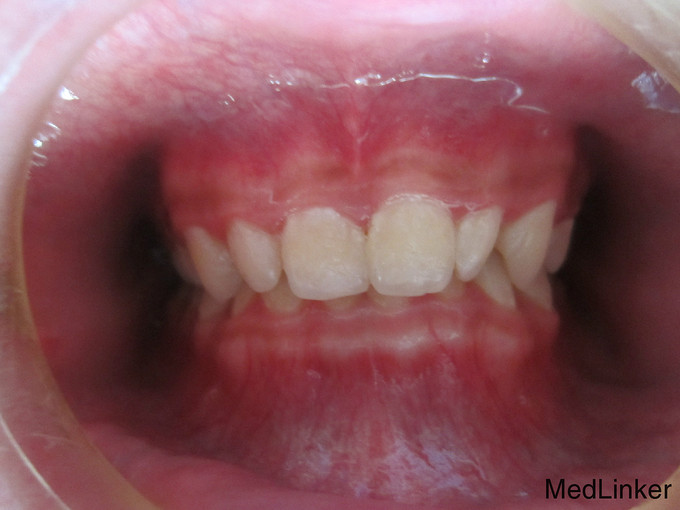

检 查:双侧颞下颌关节开口弹响,开口度一度; 模型测量分析:3度深覆合,上下颌轻度拥挤,spee曲线陡峭,上下颌尖牙尖锐、宽度较小,; 头 颅 侧位片:下颌平面角低角,下颌后缩,余正常; 辅 查:曲面断层片、头颅侧位片,双侧颞下颌关节片

诊断:深覆合、下颌后缩导致颞下颌关节负担加重,引起关节紊乱 治疗:一期:制作合平面导板,戴用一月后关节症状减轻,确定病因; 二期:带用固定矫治器,首先排齐上颌4个月,之后配合平面导板及摇椅弓排齐整平下颌5个月,调整上下颌咬合关系3个月,精细调整2个月,保 持1个月后拆除矫治器,患者自觉关节症状明显好转,制作保持器保持。